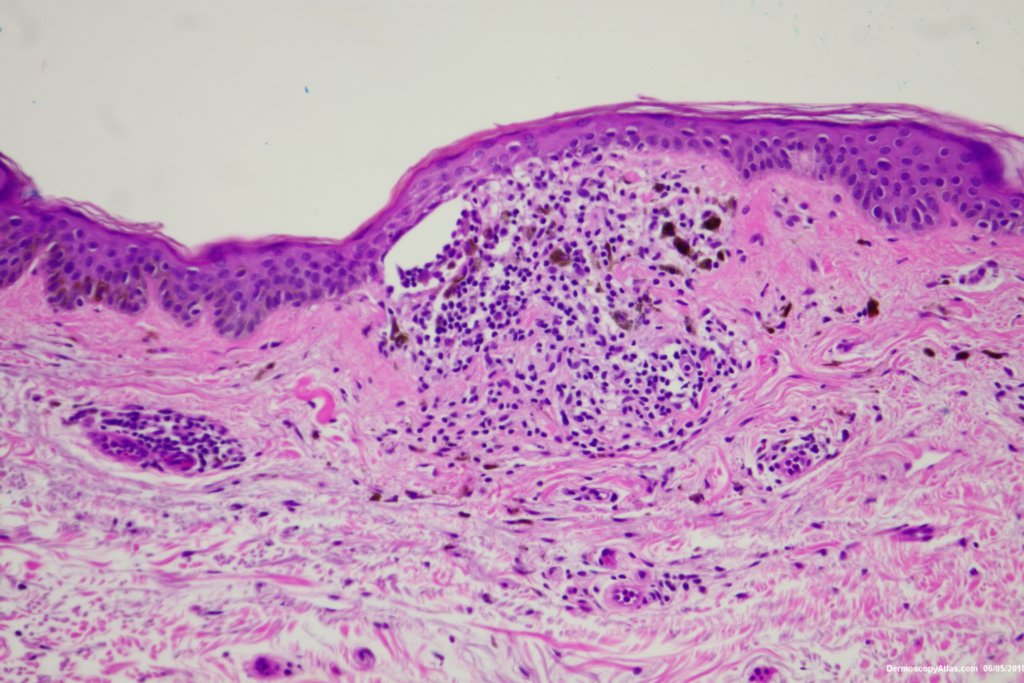

Diagnosis: Seborrhoeic keratosis

The dark areas within this seborrhoeic keratosis were dark keratin cysts. There is an associated lichenoid reaction at areas.